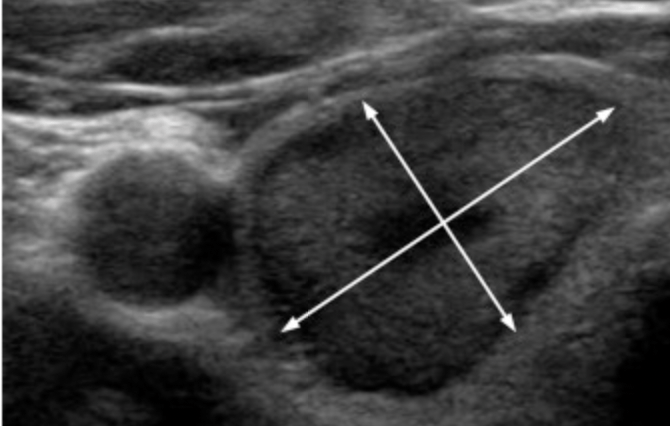

- Measurement and Documentation:

- Accurate sizing of thyroid nodules is critical, as the maximum dimension determines whether a given lesion should be biopsied or followed

- Although some interobserver discrepancy is inevitable because of variable conspicuity, consistent technique improves measurement accuracy and reproducibility

- Nodules should be measured in three axes:

- Maximum dimension on an axial image

- Maximum dimension perpendicular to the previous measurement on the same image

- Maximum longitudinal dimension on a sagittal image

- For obliquely oriented nodules, these measurements may be different than the ones used to determine a taller-than-wide shape, but this discrepancy should rarely present a problem in practice

- Measurements should also include:

- The nodule’s halo, if present

- Practitioners may use linear dimensions to determine volume, a calculation that is available on many ultrasound machines

- Regardless of the method used, each practice should measure and report nodules consistently to facilitate serial comparison